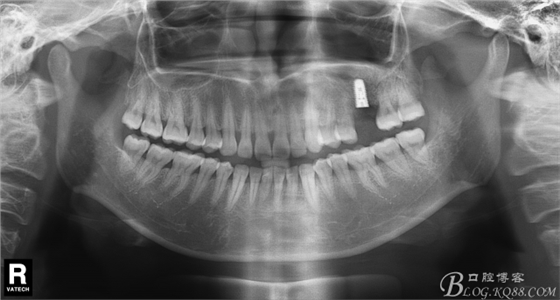

術(shù)前X片。上頜竇外提一例